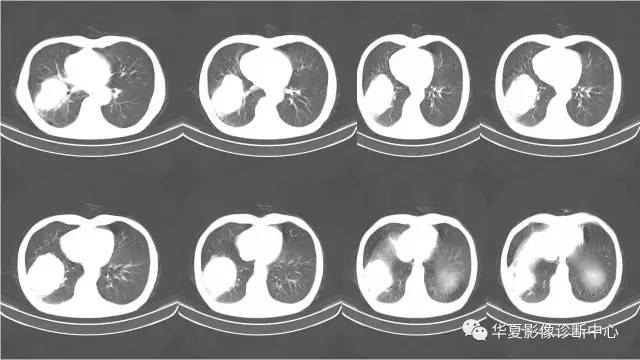

右肺原始神经外胚层肿瘤PNET一例CT